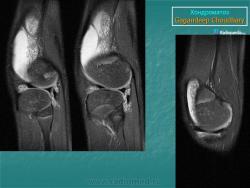

Хондроматоз внутрисуставной (синовиальный).

Хондроматоз

Хондроматоз внутрисуставной (синовиальный)